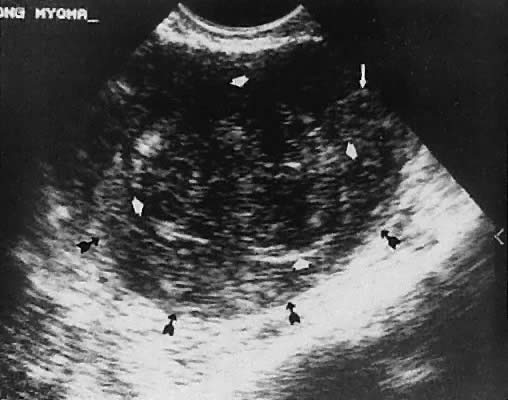

Leiomyoma. Uterine enlargement that is not caused by pregnancy most often is a result of uterine leiomyomata. Uterine leiomyomata represent proliferations of smooth muscle and are benign neoplasms. Leiomyomata are classified by their location as subserous, intramural, or submucous. Ultrasonographically, leiomyomata exhibit poor sound transmission because much of the sonic energy is attenuated by the solid consistency of the mass. Uterine contour irregularity is one of the most consistent findings44; however, a variety of findings may occur.45 Ultrasonography offers the potential of measuring uterine leiomyomata in patients in whom a conservative or nonsurgical management plan is initiated46 (Figs. 22 and 23). In addition, ultrasonography may detect early signs of degeneration or calcification of uterine leiomyomata. The effect of gonadotropin-releasing hormone suppression of uterine leiomyomata is easily monitored by ultrasonography. Occasionally, leiomyomata may undergo degeneration and mimic other cystic pelvic masses.47,48

Fig. 22. Multiple subserous uterine leiomyomata (L). Note irregularity of the uterine contour. Scan depicts cervix (C) and bladder (B)

Fig. 23. Transvaginal image of the uterine fundus ( black arrows) and a large submucous leiomyoma ( white arrowheads) and endocervical canal ( white arrow ). This scanning plane depicts longitudinal (sagittal) uterine anatomy.